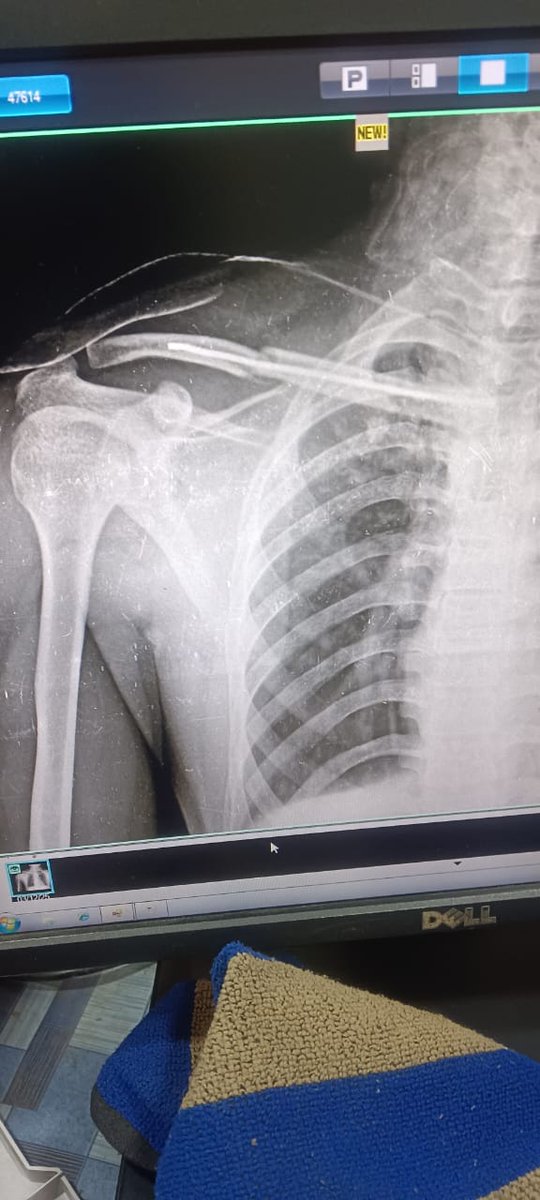

SBI ने बिना पूर्व सूचना ₹1000 काट लिए जब हम गंभीर स्वास्थ्य संकट से जूझ रहे हैं। मेरी पत्नी 8 माह की गर्भवती हैं, मेरे कंधे की हड्डी टूटी है। अब बैंक याेनो ऐप खोलो, यह करो वह करो — ऐसी बातें कर रहा है। हमें नहीं आता हमें हमारा पैसा वापस चाहिए कृपया मदद करें। State Bank of India

SBI ने बिना पूर्व सूचना ₹1000 काट लिए जब हम गंभीर स्वास्थ्य संकट से जूझ रहे हैं। मेरी पत्नी 8 माह की गर्भवती हैं, मेरे कंधे की हड्डी टूटी है। अब बैंक याेनो ऐप खोलो, यह करो वह करो — ऐसी बातें कर रहा है। हमें नहीं आता हमें हमारा पैसा वापस चाहिए कृपया मदद करें।  <a href="/TheOfficialSBI/">State Bank of India</a>